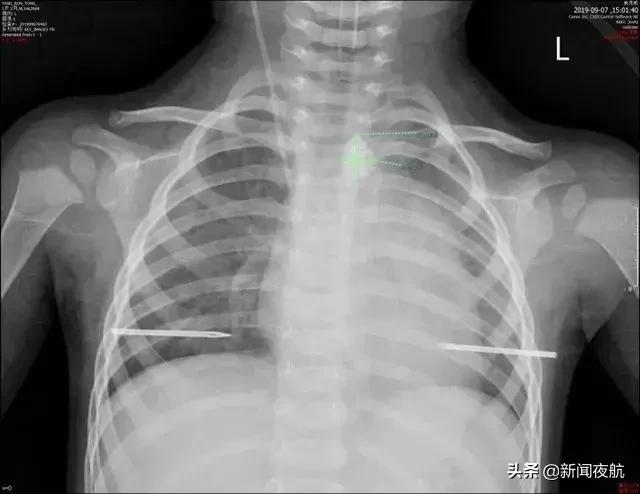

9月7日上午11时,深圳市儿童医院医生收到紧急通知,急诊收入一名1岁2个月的男孩,因“误吞碎玻璃渣3小时”入院,外院胸片检查示“食管上段异物,位于主动脉弓之上约0.7cm,大小约1.2x1.2cm”,入院诊断食管异物。

办理入院后,医生紧急安排小桐做了CT,很快CT检查结果就出来了,结果让人捏了把冷汗,食管中上段约平第2、3胸椎水平可见一不规则长条状高密度影,大小约13x16mm(左右径x上下径),相应水平食管周围间隙尚清晰。